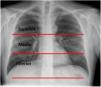

Materiales y métodosSe ha realizado un estudio retrospectivo a 292 pacientes enfermos de COVID-19 que consultaron en el servicio de urgencias, en un período de mes y medio (del 16 de marzo al 30 de abril de 2020). Para estandarizar los patrones radiológicos, hemos utilizado la escala ERVI, categorizando el patrón radiológico en leve, moderado y grave. Se ha analizado la relación entre la gravedad radiológica según la escala ERVI y la necesidad de ingreso hospitalario, en UCI y la mortalidad.

Material and methodsThis retrospective study included 292 patients with COVID-19 who presented at the emergency department between March 16, 2020 and April 30, 2020. To standardize the radiologic patterns, we used the RSEHA, categorizing the radiologic pattern as mild, moderate, or severe. We analyzed the relationship between radiologic severity according to the RSEHA with the need for admission to the hospital, admission to the ICU, and mortality.